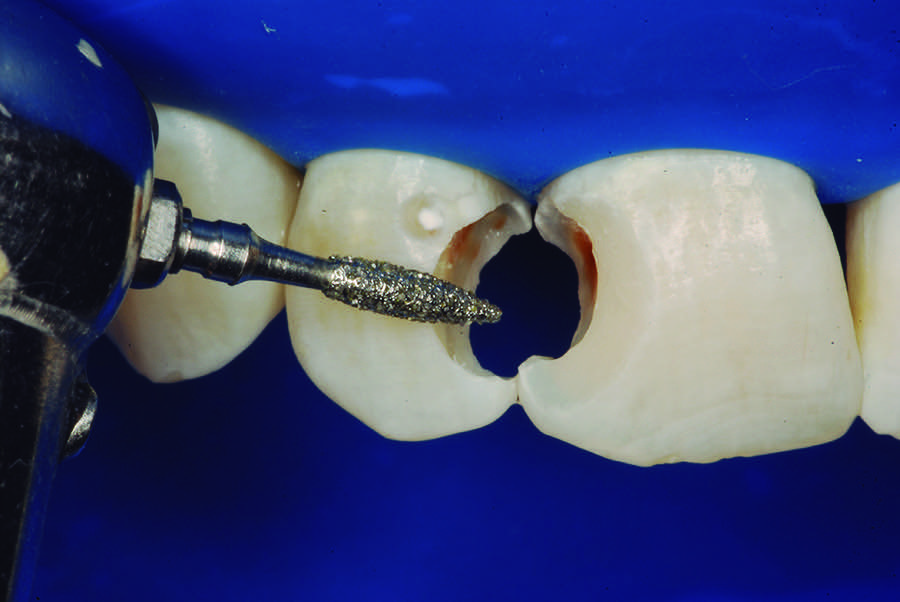

Once the maintenance of pulp vitality was verified, esthetic restorations of the teeth were performed. Initially, the teeth color shade was selected with the aid of a commonly used shade guide. After the isolation with a rubber dam, complete removal of the decayed dentin was performed in the teeth that received the stepwise excavation. The clinical verification of the presence of the mineralized barrier was performed in the maxillary lateral incisor with the aid of a disinfected gutta-percha cone, compatible with the diameter of the cavity. The authors recommend this procedure, because it allows the clinician to verify the formation of a mineralized barrier without compromising this critical area or causing a new exposure of the pulp tissue to the oral environment (Figure 11). After this, all teeth were treated with an indirect pulp capping technique. To obtain esthetics and functionality, beveling of both buccal and lingual surfaces was performed with No. 3118 diamond burs (Figure 12).

Fig 12. Enamel beveling with No. 3118 diamond bur.

Figure 12